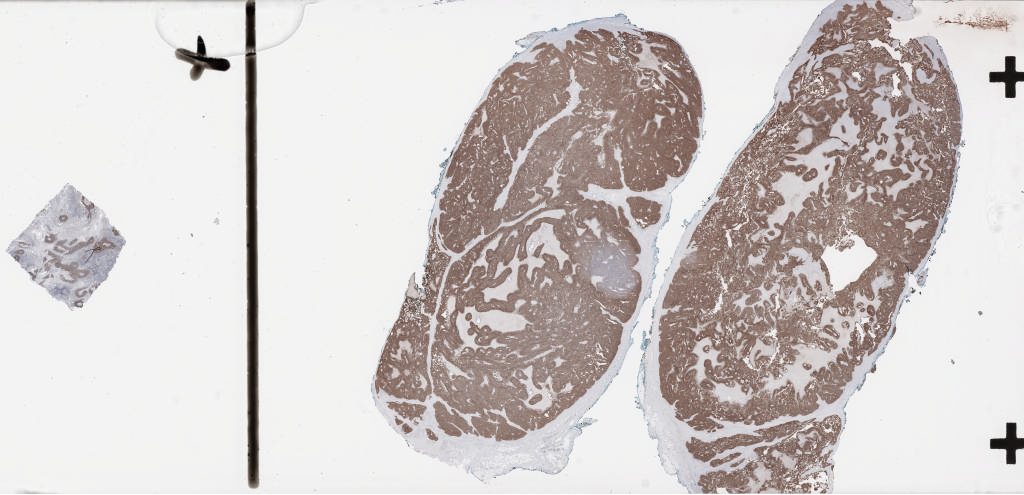

1349198.svs

193224

x

93377

@

40X